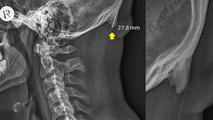

Dos estudios australianas hicieron un extraño hallazgo al examinar cientos de radiografías de cráneos y encontrar que alrededor de un tercio tenía crecimientos óseos, informó NBC News.

El estudio, que se publicó el año pasado en la revista Scientific Reports, encontró que las personas más jóvenes tenían crecimientos más grandes.

La mayoría de los espolones óseos en la base del cráneo no causan dolor y no requieren tratamiento, pero pueden convertirse en un problema si alcanzan cierto tamaño.